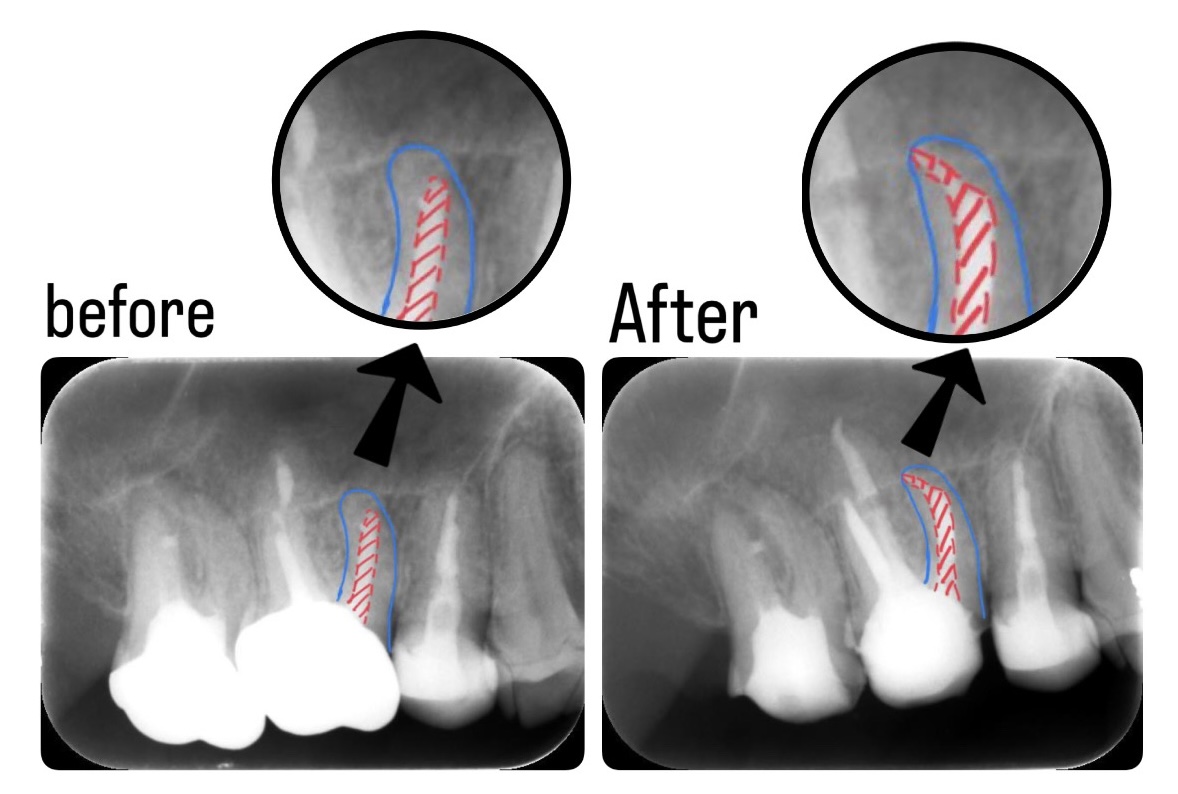

書籍詳細「長期経過症例から紐解く根尖病変と骨縁下欠損」 | フォル。書籍詳細「長期経過症例から紐解く根尖病変と骨縁下欠損」 | フォル。根の先の病気が原因で、歯茎が腫れてグラグラしている。抜歯したくない。「長期経過症例から紐解く根尖病変と骨縁下欠損 = Treatment trends and measures of periapical lesion and infrabony defect : その傾向と対策」倉富 覚、 / 下川 公一定価: ¥ 260001度も読んでいない新品ですが素人の自宅保管になりますので、完璧な新品を求めている方は落札をご遠慮下さい。他にも多数出品しておりますので是非宜しくお願い致します。自己紹介文を必ず読んでから購入お願い致します。#倉富覚、 #倉富_覚、 #下川公一 #下川_公一 #本 #自然/医療・薬学・健康。第47回北九州歯学研究会発表会開催 - クインテッセンス出版。看護管理学習テキスト 第3版 2025年版 5冊セット。セーフティテクニック 心臓手術アトラス 原書第3版

• 根の先の病気が原因で、歯茎が腫れてグラグラしている。抜歯したくない